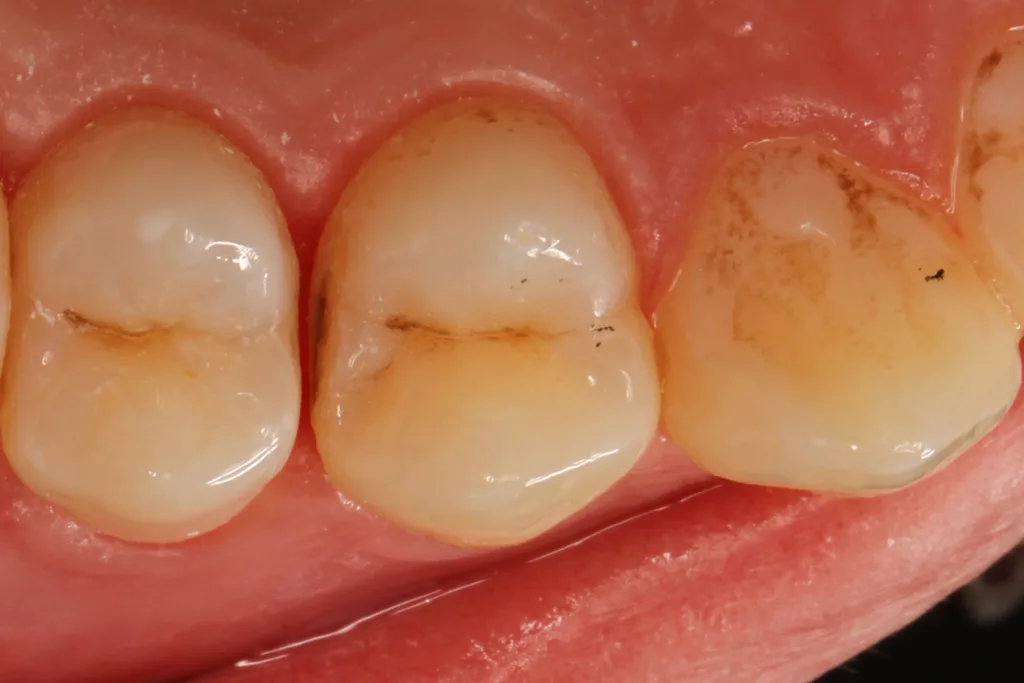

Fall 2: Versorgung einer Initialkaries an Zahn 14 und später an 15

Die 26 Jahre alte Patientin störte sich an der approximalen Lücke zwischen den Zähnen 14 und 15, da sich hier ständig Speisereste impaktierten. Bei der klinischen Inspektion fiel die Initialkaries distal an Zahn 14 auf (Abb. 7). Die Patientin wurde dahingehend beraten, den Spalt mit einer minimalinvasiven Kompositrestauration zu versorgen – bei zeitgleicher Exkavation der Karies an Zahn 14. Nach Exkavation und Präparation des Defektes (der sich als deutlich ausgeprägter präsentierte als anfangs angenommen) erfolgte identisch zu Fall 2 die Ausformung der Kavität mit einer Teilmatrize (Danville ultra thin flex), einem Kunststoffkeilchen (G-Wedge) und der Separation mit einem NiTin-Prämolaren-Spannring (re-invent, Abb. 8).

Teilmatrizensysteme stellen heutzutage die erste Wahl in der Gestaltung anatomischer Kontaktflächen dar [22]: Sie garantieren korrekte anatomische Formen, straffe Approximalkontakte und belastungsoptimiert ausgeformte Randleisten [74–76]. Nach der adhäsiven Vorbehandlung (G2 Universal, GC, total etch) wurde der Defekt identisch zum vorherigen Fall mit dem niedrigviskösen Visalys Bulkflow in einem Zug aufgefüllt und mit der Sondenspitze ausmodelliert (Abb. 9). Die Aushärtung (Elipar Deep Cure) erfolgte erneut standardisiert für jeweils 20 Sek.: einmal okklusal zentral nach Einbringen des Bulkflow-Materials und je einmal als Nachhärtung nach Abnahme der Matrizen-Verschalung aus bukkaler und erneut okklusaler Richtung mit genau auf der Randleiste positioniertem Lichtgerät. So wird mit Sicherheit eine suffiziente Aushärtung des 4 mm tiefen Defektes gewährleistet.

Die Abbildung 10 zeigt das Behandlungsergebnis unmittelbar nach Ausarbeitung und Politur (Diacomp Plus Twist, EVE), die Abbildung 11 bei einer weiteren Kontrolle nach sechs Monaten. In diesem Kontrolltermin wurden dann im routinemäßigen, zwei- bis dreijährigen Intervall Bissflügelröntgenaufnahmen zur Kariesdiagnostik angefertigt. Auf der Röntgenaufnahme zeigt sich die neue Visalys-Bulk-Flow-Restauration als randdicht, anatomisch korrekt geformt und ausreichend röntgenopak (Abb. 12). Die Schmelzläsion mesial an den Zähnen 15 und 16 erschien nicht therapiebedürftig, da die Oberfläche intakt war, wohl aber die versteckte Dentinläsion distal an dem Zahn 15. Der Defekt wurde in einem weiteren Termin identisch mit denselben Materialkombinationen und identischem Polymerisationsprotokoll versorgt (Abb. 13 bis 15).